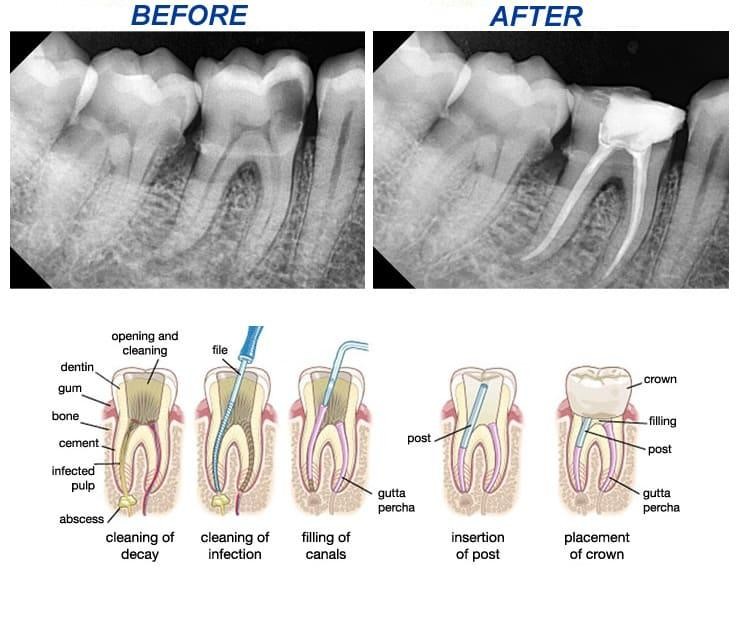

Root canal treatment (RCT) is a dental procedure used to remove

infected or damaged pulp (the soft tissue inside your tooth). The

area is cleaned, disinfected, and sealed to save the natural

tooth.

4. Dental X-Rays (Most Important Step)

X-rays play a crucial role in diagnosing the need for RCT

treatment. They help dentists see:

- Infection at the root tip

- Bone loss around the tooth

- Deep cavities reaching the pulp

If the infection is visible on an X-ray, root canal treatment in

Bangalore is usually necessary.

Life After Root Canal Treatment

After a successful RCT treatment, you can:

- Eat normally without pain

- Preserve your natural tooth

- Avoid further complications

- Maintain better oral health

A crown is often placed on the treated tooth to restore strength

and function.